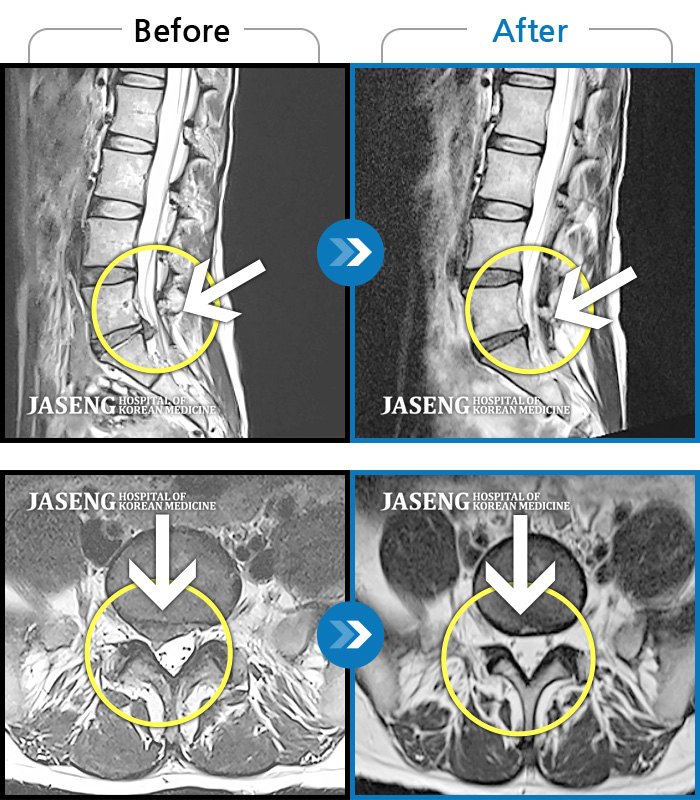

Before

After

환자에게 사전 동의를 받아 동일 조건에서 촬영되었습니다.

개인에 따라 치료 후 부작용이 발생할 수 있으니 의료진과 상담 후 치료를 진행하시기 바랍니다.

"허리디스크 치료하는 동안 예전에 치료 받았던 목디스크도 확인해보고 싶어요”

우측 다리가 저리고 감각이 둔함